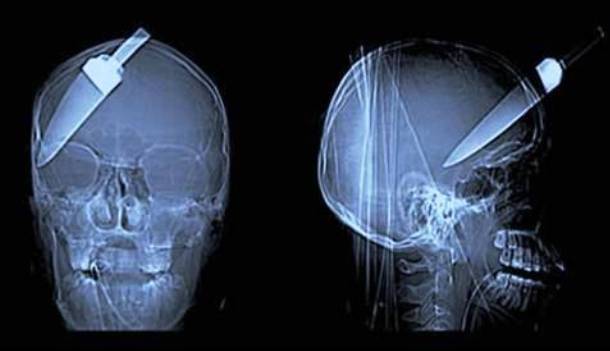

12. A Knife To The Eye

This soldier had a knife in his head as we can see here in the x-ray photo. And, somehow despite it penetrating 4 inches right into his head - just above his eyebrow the soldier still somehow managed to survive during the operation without any other complications.Advertisement